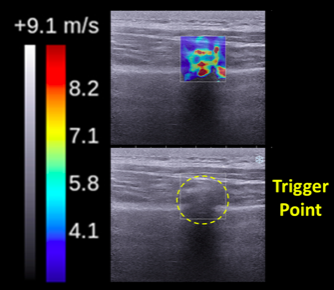

2. Часто проблема видна на снимках УЗИ. Помимо классических МРТ и КТ, УЗИ-диагностика порой более информативна и при этом провести исследование гораздо легче. Помимо классического УЗИ, самое последнее время при диагностике мягких тканей делают эластографические исследование – один из видов ультразвукового исследования, измеряющее количественную жесткость тканей, свойство, не видимое на обычном УЗИ-изображении. Такую диагностику пока применяют экспериментально, но даже без необходимых международных метрик жесткости можно многое понять по эластографическому изображению. На рисунке 1 изображена триггерная точка на обычном УЗИ-изображении и эластографической картинке, где от синего к красному по шкале повышается жесткость тканей. Можно обратить внимание, что на УЗИ-изображении триггерная точка и ее форма, представляющая собой жёсткий соединительнотканный тяж из фиброзной ткани, практически не видна.

Рисунок 1. Триггерная точка на обычном УЗИ-изображении и при эластографической визуализации